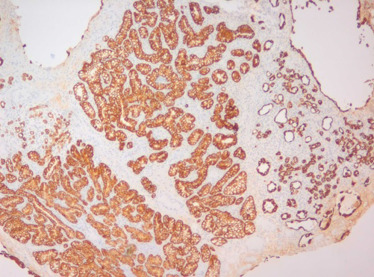

Estudo imunohistoquímico – expressão de citoqueratina 7; (100x).

Figura 3.

Estudo imunohistoquímico – expressão de citoqueratina 7; (100 x).

Estudo imunohistoquímico – expressão de P504s (alfa‐methylacyl coenzime‐A ...

Figura 4.

Estudo imunohistoquímico – expressão de P504s (alfa‐methylacyl coenzime‐A racemase [AMARC]); (200 x).